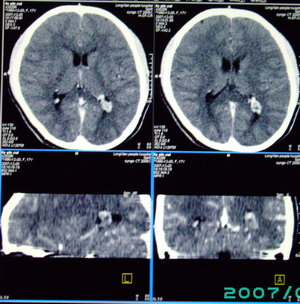

以下是引用九目段在2007-12-24 14:55:00的发言:[br]1,年轻女性[br]2,ct表现:左侧脑室三角区可见一不规则小明显强化的结节,中央见小低密度,侧脑室无扩张。[br]分析:[br]常见的有三种肿瘤好发三角区:[br]1,脉络丛乳头状瘤,好发于年轻者,明显强化,实性,分泌脑脊液,常伴有侧脑室扩大,肿瘤较小可以脑室扩大不明显,不能排除,但小结节尚不易形成坏死腔。[br]2,室管膜瘤,好发于儿童及青少年,明显强化,易坏死,大时伴脑室扩张。[br]3,脑膜瘤,明显强化,圆形,界请,无脑积水,一般不坏死。[br]诊断:[br]左侧脑室三角区结节,考虑室管膜瘤可能性大,不排除脉络丛乳头状瘤和脑膜瘤(因病史较长)。[br][br][本贴已被 九目段 于 2007-12-24 15:13:35 修改过]